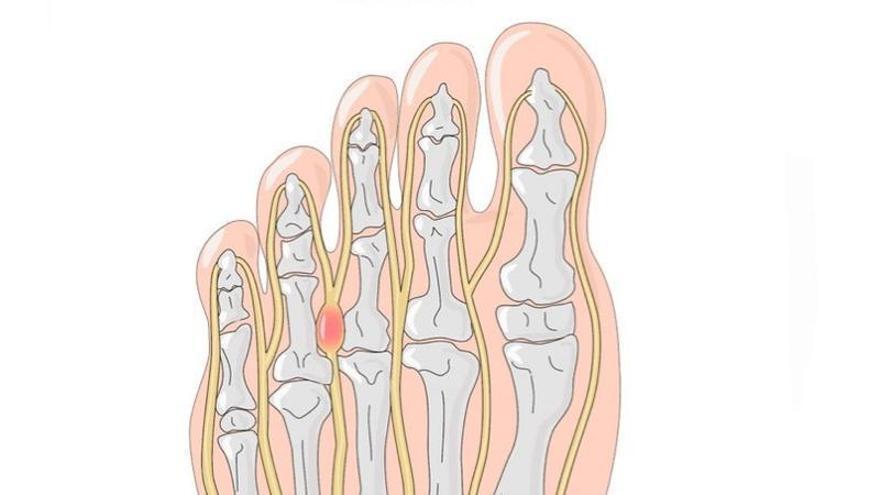

El Neuroma de Morton és un engruiximent en forma de fibrosi, d’un nervi interdigital plantar a l’alçada dels caps metatarsians. El més usual és que aparegui entre el tercer i el quart metatarsià, tot i que també pot estar present en els altres espais intermetatarsians. Aquesta fibrosi, considerada com a tumoració benigna, és la causant de la simptomatologia.

La irritació o compressió d’aquesta zona del nervi és la que causa la simptomatologia. Un calçat massa estret pot provocar el pinçament d’aquest nervi entre els dos metatarsians. També un taló massa elevat pot afavorir els símptomes, pel desplaçament anterior del peu dins de la sabata i l’augment de la compressió lateral.

Els símptomes derivats del neuroma de Morton són característics. La sensació de coïssor a la zona metatarsiana o dolor tipus elèctric que pot irradiar-se cap als dits és habitual. A vegades poden aparèixer parestèsies o sensació de formigueig i falta de sensibilitat als dits.